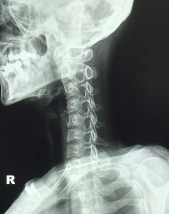

거북목 증후군 증상 원인 치료방법 알아보아요 거북목 증후군 증상 원인 치료방법 등 거북목에 대한 정보를 알아보도록 하겠습니다.

거북목은 목의 자세가 앞으로 구부러지면서 등에 부담을 주는 자세로 인해 발생하는 질환입니다. 주로 스마트폰, 태블릿, 노트북 사용 등으로 인해 긴 시간을 앉아있는 경우나, 운전, 쓰기 등과 같이 앞을 보며 일하는 경우에 발생할 수 있습니다.

거북목은 목과 어깨 근육의 긴장으로 인해 두통, 목 아픔, 어깨 아픔 등의 증상을 유발할 수 있습니다. 또한 이 자세로 인해 목 뒤쪽의 인대와 근육이 변형되거나 손상될 수도 있습니다.